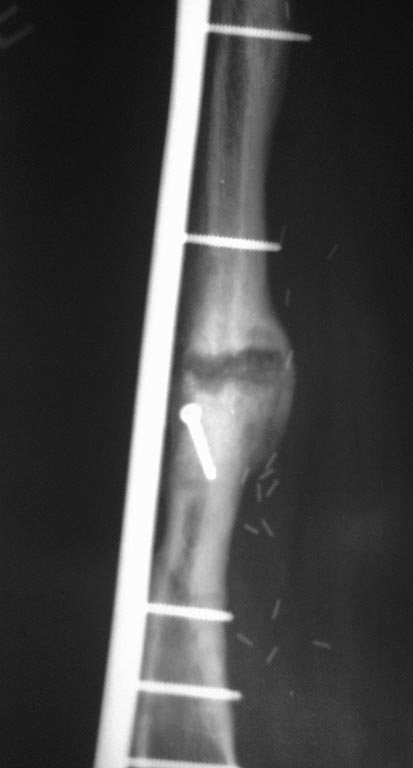

Уважаемые коллеги, нужен совет. Девочка, 18 лет, остеогенная саркома 2010 год, резекция, замещение свободным васкуляризированным трансплантатом малоберцевой кости с остеосинтезом L-образной пластиной. Пластина удалена в 2011 году после консолидации концов трансплантата и проксимальных и дистальных концов бедренной кости (хотя нестабильность конструкции, миграция винтов имело место быть. В 2012 году несколько переломов трансплантата, лечение консервативное. Сентябрь 2012 после очередного перелома открытая репозиция, костная аутопластика кортикально-губчатым трансплантатом из крыла подвздошнй кости с МОС пластиной с угловой стабильностью. Интраоперационно - без особенностей. В период динамического наблюдения на фоне образования костной мозоли отмечается литическая деструкция концов костных отломков в зоне перелома (снимки - 1 мес, 2.5 мес и 3.5 мес после операции. Что это? Метастаз? Откуда (из крыла?) Нестабильность(признаков нет..)? Какую тактику посоветуете? Спасибо.

пластина по индивидуальному заказу, все винты с угловой стабильностью, дистально, по моему, винтов 7 - 8 (аналог дистальной мыщелковой пластины). Толщина винтов в средней части определялась толщиной трансплантата малоберцевой кости. Отдельный кортикальный винт в с/3 - фиксация аутотрансплантата крыла бок в бок. в плане нестабильности - деформации винтов, их миграции, резорбции костной ткани вокруг них нет. Смущает кистообразная литическая полость в зоне перелома с тенденцией к увеличению . Пока дали антирезорбенты...